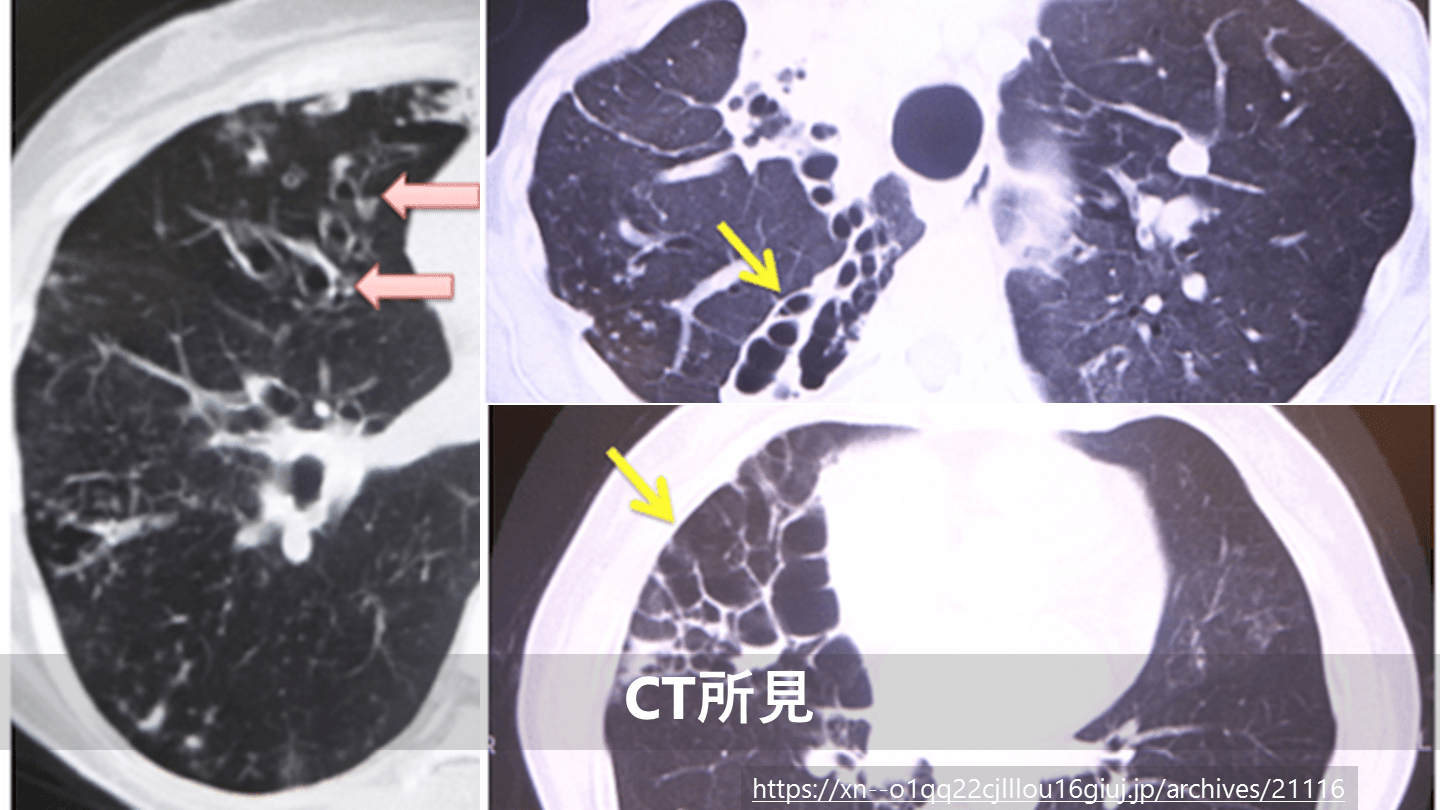

気管支拡張症のCT所見と検査

#15.

異常所見 Clinical manifestations and diagnosis of bronchiectasis in adults, UpToDate, last updated Sep 20, 2019. 気管支壁の 肥厚と拡張